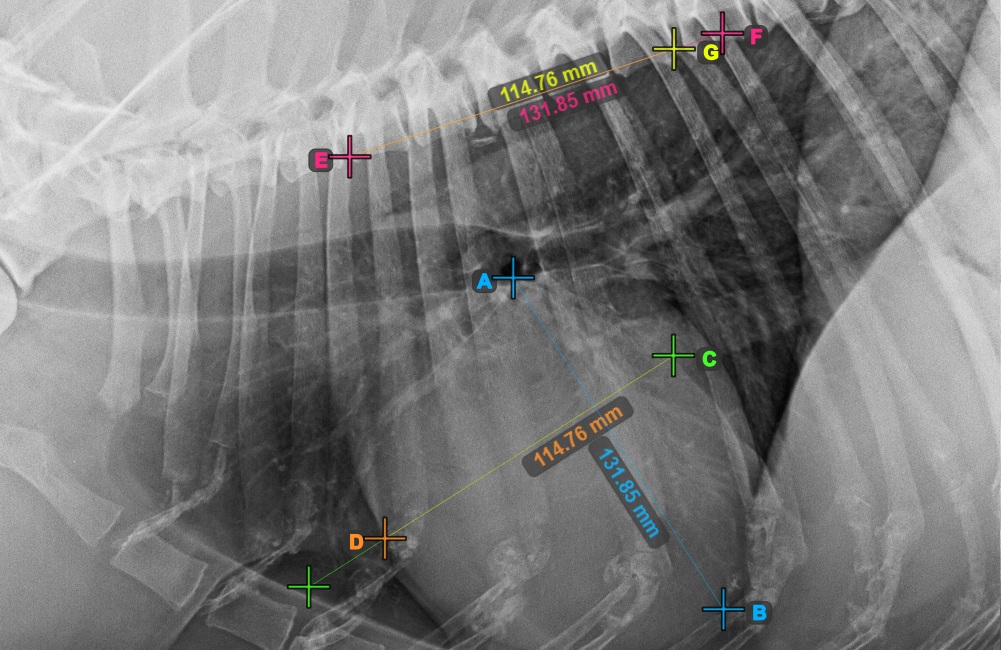

Complete the long axis of the heart by marking the Apex point, near the bottom of the heart.

The image below represents a typical placement of the Apex point.

Continue the measurement by marking the widest right (cranial) point of the short axis of the heart.

The image below represents a typical placement of the most cranial point on the short axis of the heart.

Complete the short axis of the heart by marking the widest left (caudal) point.

The image below represents the typical placement of the most caudal point on the short axis of the heart.